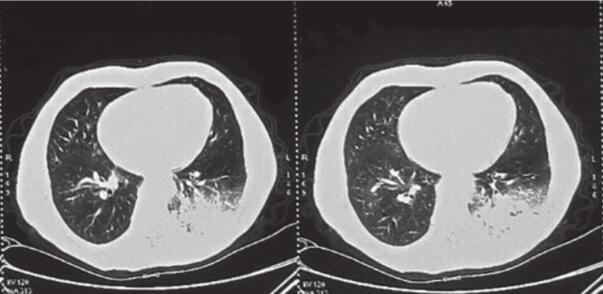

患者,刘某,男,66岁。因“反复咳嗽、咳痰2年余,再发加重3天”于2014年3月7日入院。自2012年以来,患者无明显诱因出现反复咳嗽、咳痰,多为白色泡沫痰,咳嗽剧烈时伴胸闷、气喘不适,间断高热,多次在外院住院治疗,每经抗感染及止咳祛痰等对症治疗后病情可缓解,出院后患者咳嗽、咳痰症状仍反复。自2012年起病以来,患者多次行肺部CT(图1~图4)检查提示“左下肺大片状及右上叶片状阴影”,行抗感染治疗后右肺上叶稍吸收,左下肺片状影吸收欠佳。2013年8月考虑患者“肺结核”不能排除,在本市结核病医院,查T-spot(+),后给予三联抗结核(异烟肼+利福平+乙胺丁醇)治疗2个月,咳嗽、咳痰未见明显好转。2013年11月曾因咳嗽、咳痰加重入我科,给予抗感染(左氧氟沙星)及继续抗结核(异烟肼+利福平+乙胺丁醇)治疗,期间患者因大便潜血(+)行肠镜检查,提示“乙状结肠直肠新生物”,病理检查示“乙状结肠腺癌”,于2013年12月8日转普外科行“乙状结肠癌根治术”。此次入院前3天,患者受凉后再发咳嗽,咳白色泡沫痰,量较多,偶为粉红色泡沫痰,咳嗽剧烈时感憋气、胸痛,无畏寒、发热,无恶心、呕吐,无双下肢水肿等不适。

图2 2013年8月27日肺部CT

图3 2013年10月21日肺部CT